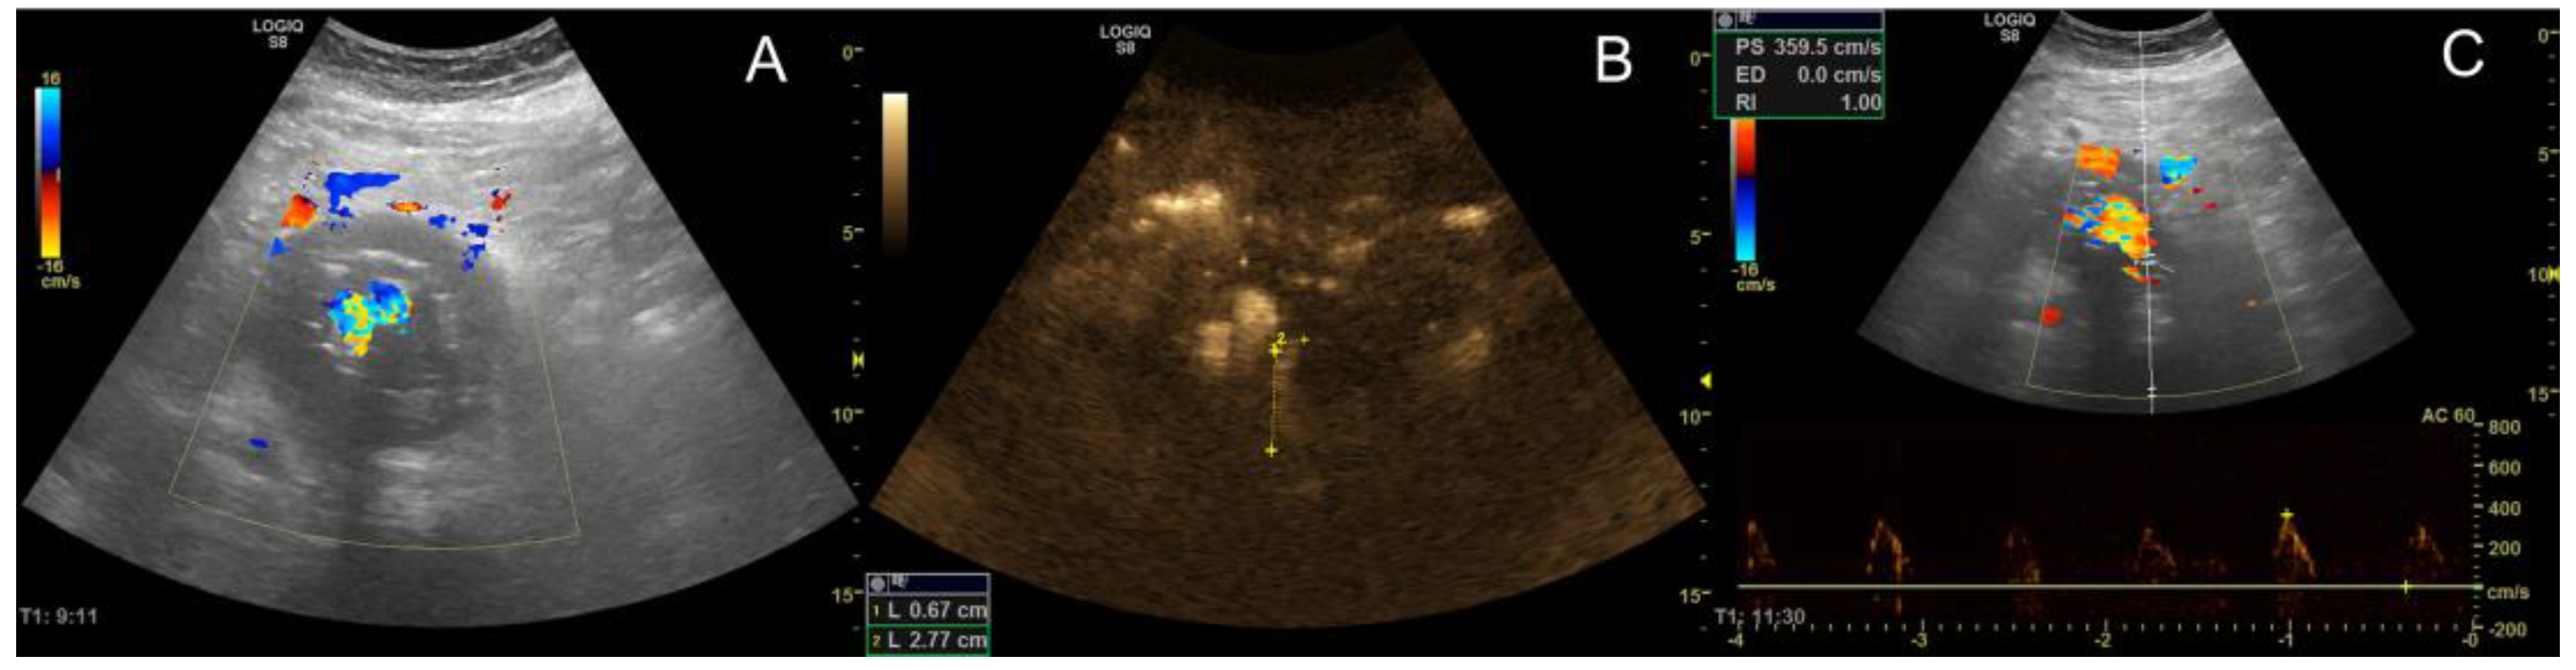

- Cantisani, V.; David, E.; Ferrari, D.; Fanelli, F.; Di Marzo, L.; Catalano, C.; Benedetto, F.; Spinelli, D.; Katsargyris, A.; Blandino, A.; et al. Color Doppler Ultrasound with Superb Microvascular Imaging Compared to Contrast-enhanced Ultrasound and Computed Tomography Angiography to Identify and Classify Endoleaks in Patients Undergoing EVAR. Ann. Vasc. Surg. 2017, 40, 136–145. [Google Scholar] [CrossRef] [PubMed]

- Gabriel, M.; Tomczak, J.; Snoch-Ziółkiewicz, M.; Dzieciuchowicz, Ł.; Strauss, E.; Pawlaczyk, K.; Wojtusik, D.; Oszkinis, G. Superb Micro-vascular Imaging (SMI): A Doppler ultrasound technique with potential to identify, classify, and follow up endoleaks in patients after Endovascular Aneurysm Repair (EVAR). Abdom Radiol. 2018, 43, 3479–3486. [Google Scholar] [CrossRef]

- Curti, M.; Piacentino, F.; Fontana, F.; Ossola, C.; Coppola, A.; Marra, P.; Basile, A.; Ierardi, A.M.; Carrafiello, G.; Carcano, G.; et al. EVAR Follow-Up with Ultrasound Superb Microvascular Imaging (SMI) Compared to CEUS and CT Angiography for Detection of Type II Endoleak. Diagnostics 2022, 12, 526. [Google Scholar] [CrossRef]

- Hofmann, A.G.; Mlekusch, I.; Wickenhauser, G.; Assadian, A.; Taher, F. Clinical Applications of B-Flow Ultrasound: A Scoping Review of the Literature. Diagnostics 2023, 13, 397. [Google Scholar] [CrossRef]